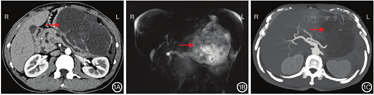

患者男,50岁。因腹上区胀痛3 d于2018年12月20日入院。患者4年前曾出现腹上区阵发性绞痛,向右侧腰背部放射,伴恶心呕吐,呕吐物为胃内容物。发作时至当地医院行CT检查示急性胰腺炎,血淀粉酶>正常值上限3倍,行胃肠减压及抑制胰酶等治疗,疼痛消失后出院。其后胰腺炎未复发。此次入院前3 d患者再次出现腹上区疼痛,伴腹胀,无恶心呕吐、发热等不适。遂至我院检查,门诊行腹上区CT检查平扫示:主胰管扩张,胰腺体尾部囊性病灶。患者自发病以来,精神、饮食一般,大、小便正常,体质量无明显下降。患者否认肝炎病史,2017年8月17日因脑血管瘤破裂行相关手术,具体不详。入院体格检查:一般情况尚可,皮肤、巩膜无黄染,浅表淋巴结未触及肿大,心肺未见明显异常,腹软,腹上区饱满,有压痛,无反跳痛,未见明显包块,肝脾肋下均未触及,肝区无叩击痛,墨菲征阴性,双肾区无叩击痛。患者入院后积极完善相关检查,血常规、血生化、凝血功能未见明显异常,HBsAg 0.14 IU/mL,HBV-DNA阴性,Alb 34.6 g/L。肿瘤标志物:CEA 475.50 μg/L、CA19-9>1 000 U/mL及CA125 54.61 U/mL,AFP 2.38 μg/L。血淀粉酶115 U/L。腹部CT检查增强扫描示:胰头饱满,主胰管扩张,于胰腺体尾部变细,胰体尾旁可见类圆形低密度影,边界清晰,壁较厚,其内可见分隔,局部见斑片状钙化,大小约14.4 cm×8.4 cm,囊性部分未见明显强化,分隔可见强化。未见累及脾脏。考虑假性囊肿(图1A)。MRCP检查结果示:胰腺体尾部可见不规则形巨块长T2信号影,内信号欠均匀,较大层面约为12.4 cm×14.8 cm,与胰腺分界不清晰,其内可见絮状分隔及小结节状壁结节影,病灶与胰管似相通,邻近胃及脾脏受压移位改变,边界清晰。结合病史及相关实验室检查结果,考虑胰腺导管内乳头状黏液癌,低度恶性(图1B)。三维重建示:胰腺体尾部后缘巨块状囊实性病灶,其内片絮状分隔及小结节状壁结节影,病灶与胰管似相通,大小约14.3 cm×10.5 cm×11.8 cm,CT检查增强扫描囊性部分未见明显强化,结合病史及相关实验室检查,考虑胰腺导管内乳头状黏液癌,低度恶性(图1C)。术前EUS检查结果示:胰腺体尾部可见一巨大的囊实性混杂偏高回声团块,边界不清晰,内部回声欠均匀,胰管全程明显扩张、不规整,最大直径约0.74 cm,内未见强回声。胆总管无扩张,未见异常回声。胆囊未探及。采用穿刺针对胰腺体尾部病灶穿刺3次,抽出淡黄色黏液,病理学检查结果示:黏液性囊腺癌待排。结合病理学检查结果、影像学及实验室检查结果诊断为胰腺导管内乳头状黏液癌,行手术治疗。